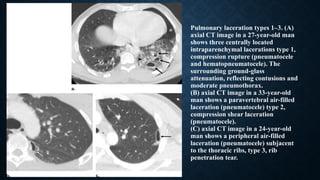

PULMONARY LACERATIONS

• Pulmonary laceration occurs in major chest trauma when disruption and tearing of the lung parenchyma follows

shearing forces, caused by direct impact, compression or inertial deceleration.

• Classified into the following four types according to the mechanism of injury:

• type I - compression rupture: most common type of laceration that usually occurs as a 2-8 cm lesion in the

central lung.

• type II - compression shear: occurs after sudden compression of the lower chest when the lung suffers from a

shear injury to the spine; the lung is compressed by lateral compression, against the spine leading to a

paravertebral tubular lesion in lower part of the lung.

• type III - direct puncture / rib penetration: occur with a penetrating fractured rib; these lesions are commonly

multiple.

• type IV - adhesion tears: occurs in sudden injuries of the chest wall where prior pleuropulmonary adhesions

have been created.